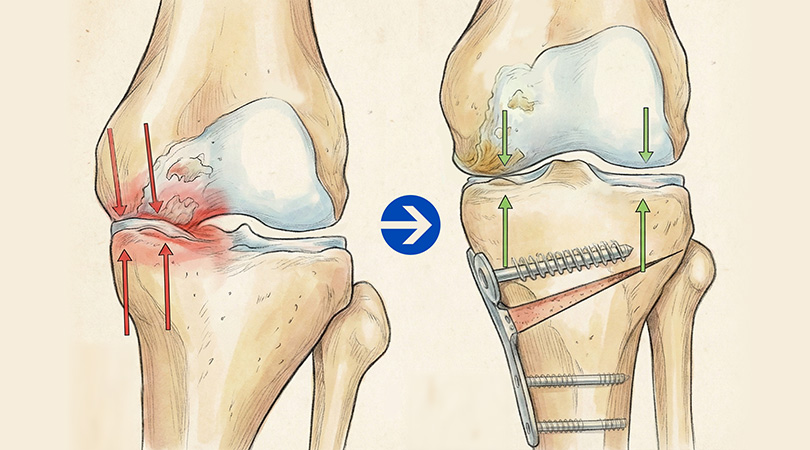

최소절개 무릎 절골술 과정

-

01

정강이뼈(경골) 윗부분을 약 3~5cm 절개한 뒤, 정강이뼈에 금을 냅니다.

02

정강이뼈 윗부분을 미세하게 벌려 인공뼈를 넣을 공간을 만들어줍니다.

03

벌려진 공간에 인공뼈를 넣어 틀어져 있던 다리 축을 정상 각도로 바로잡습니다.

04

바로잡은 각도가 잘 유지되도록 금속 플레이트와 나사로 단단히 고정합니다.